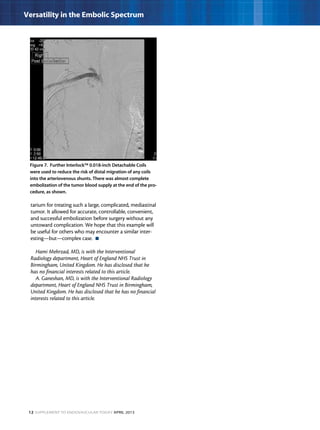

Figure 7. Further Interlock™ 0.018-inch Detachable Coils

were used to reduce the risk of distal migration of any coils

into the arteriovenous shunts. There was almost complete

embolization of the tumor blood supply at the end of the pro-

cedure, as shown.

DISCUSSION

In this selective case, we found that the Renegade STC®

Microcatheter and Interlock™ Detachable Coil system

were very useful tools in the interventional armamen-

tarium for treating such a large, complicated, mediastinal

tumor. It allowed for accurate, controllable, convenient,

and successful embolization before surgery without any

untoward complication. We hope that this example will

be useful for others who may encounter a similar inter-

esting—but—complex case.  n